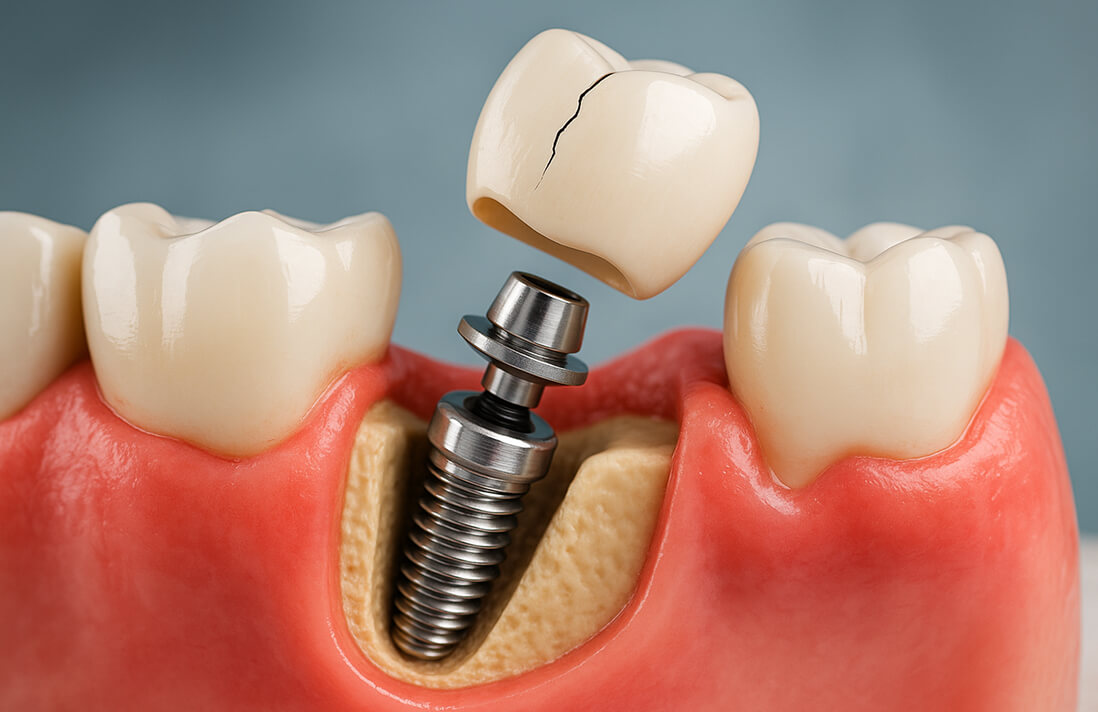

インプラント体

(顎の骨に埋める部分)の寿命チタン製のインプラント体自体は、骨としっかり結合すれば半永久的に機能すると言われています。劣化したり虫歯になったりすることはありません。

上部構造(人工歯)の寿命

セラミックなどの素材で作られた被せ物は、強い衝撃や経年変化で欠けたり、すり減ったりすることがあります。一般的に10年〜20年程度が目安ですが、問題が起きた場合は上部構造だけを交換することも可能です。

つまり、「インプラントの寿命」とは、主にインプラント体とそれを支える顎の骨が、

いかに健康な状態を保てるかどうかにかかっています。

上部構造(被せ物)の破損

インプラント体や顎の骨に問題がなければ、上部構造を作り直して交換するだけで済みます。上部構造の費用は、素材によって異なります。

インプラント周囲炎による脱落

インプラントが抜けてしまった場合、まずはインプラント周囲炎の治療を行います。その後、お口の中の状態が良好であれば、骨を増やす治療(骨造成)などを経て、再手術(インプラントの再埋入)します。